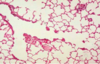

What is pulmonary oedema?

Accumulation of fluid in the alverolar spaces either due to leaky capillaries or back pressure from a failing left ventricle

This leads to poor gas exchange

What is the main histological feature of pulmonary oedema?

Intra-alveolar fluid